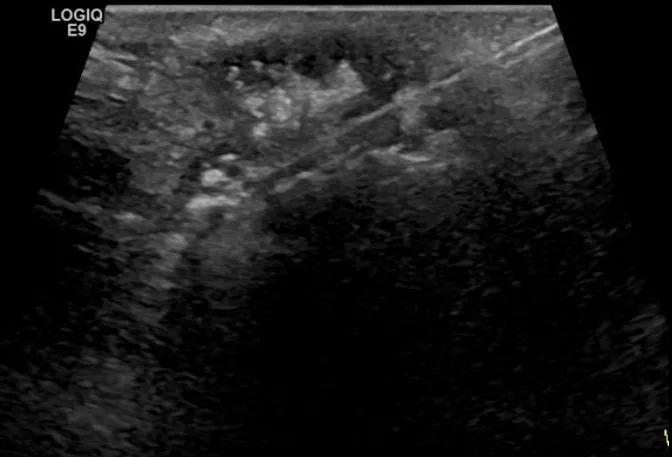

随后,徐栋教授进一步分享了五个临床实战病例,带来了更直观的热消融治疗经验。第一个病例是62岁肺癌患者,术后1年余发现双侧锁骨上淋巴结复发,侵犯神经,存在静脉回流、淋巴回流障碍,肿胀、疼痛非常明显。影像显示患者淋巴结边界不清、形态不规则,存在浸润,血流强化增强。由于患者在系统治疗后进展,且主要目的缓解症状、减瘤。局麻下行热消融术,从后向前逐层消融,热消融之后超声造影即刻评估显示完全充盈缺损,完全覆盖病灶。

(病例1图例)